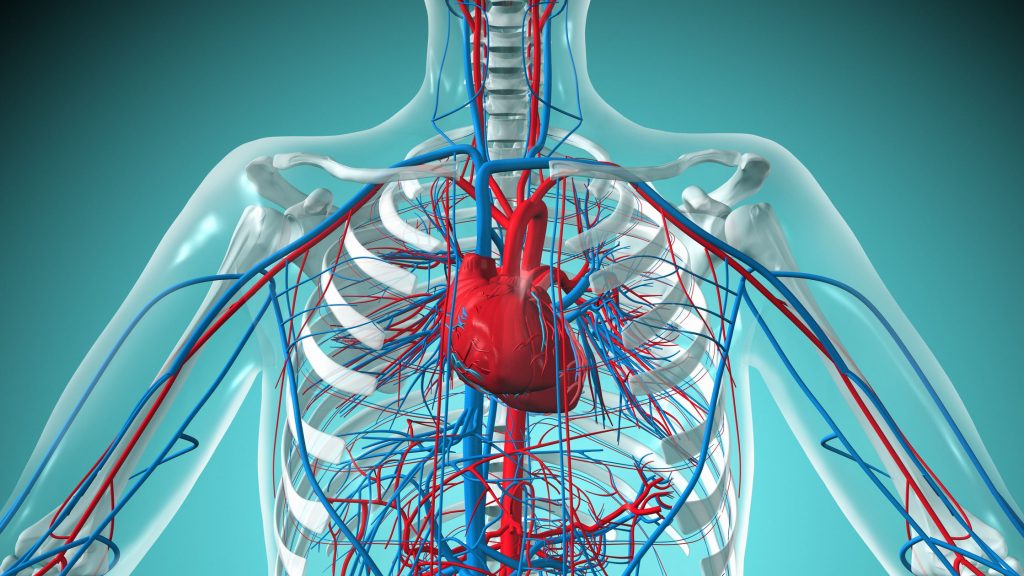

Cirkulacija je proces kretanja krvi kroz krvne sudove uz pomoć srca. Ona omogućava:

- dopremanje kisika i hranjivih materija

- uklanjanje ugljen-dioksida i toksina

- regulaciju tjelesne temperature

- podršku imunološkom sistemu

Bez pravilne cirkulacije, tijelo ne može optimalno funkcionisati.